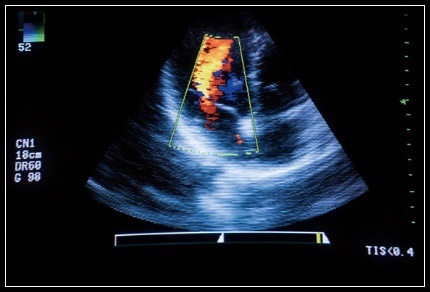

이번 보장성 강화 조치에 따라 그간 대부분 비급여로 시행되던 여성생식기 초음파 검사의 건강보험 적용 범위가 확대되어 연간 약 600~700만 명이 건강보험 혜택을 받을 것으로 전망됩니다. 또한 기존에 보험적용을 확대한 상·하복부 초음파와 동일하게 원칙적으로 의사가 실시하되, 의사가 방사선사와 동일한 공간에서 방사선사의 촬영 영상을 동시에 보면서 실시간 지도와 진단을 하는 경우 보험을 적용합니다.